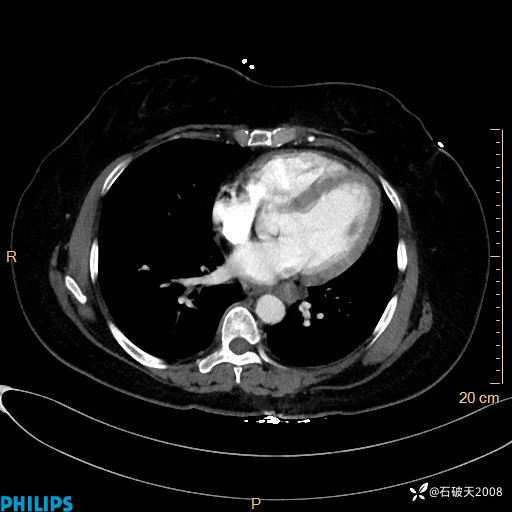

肺窗

纵隔窗